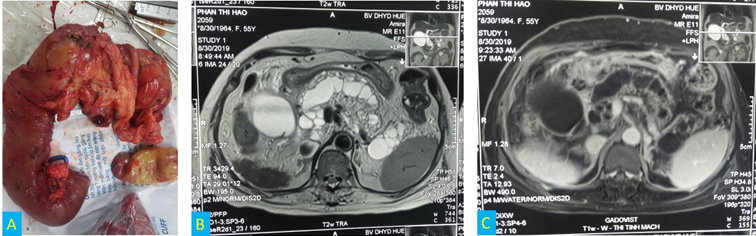

Hình 2. Khối tá tụy sau khi cắt bỏ và hình ảnh T1, T2 của phim MRI gadovist.